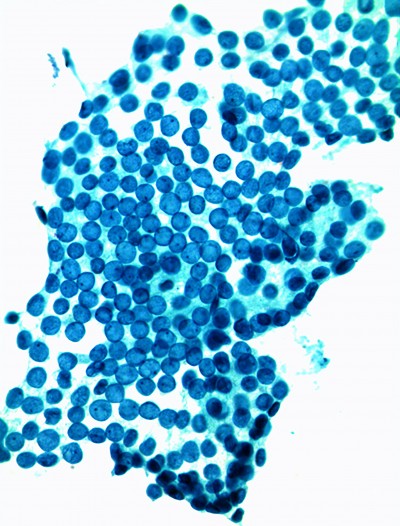

The Milan System for Reporting Salivary Gland Cytopathology

Salivary gland cytology presents many diagnostic challenges. Salivary gland tumors are one of the most heterogeneous groups of neoplasms, and salivary gland tumors are one of the most difficult areas of evaluation in cytology. The FNA sensitivity is between 86-100% with specificity somewhere between 48-94%.